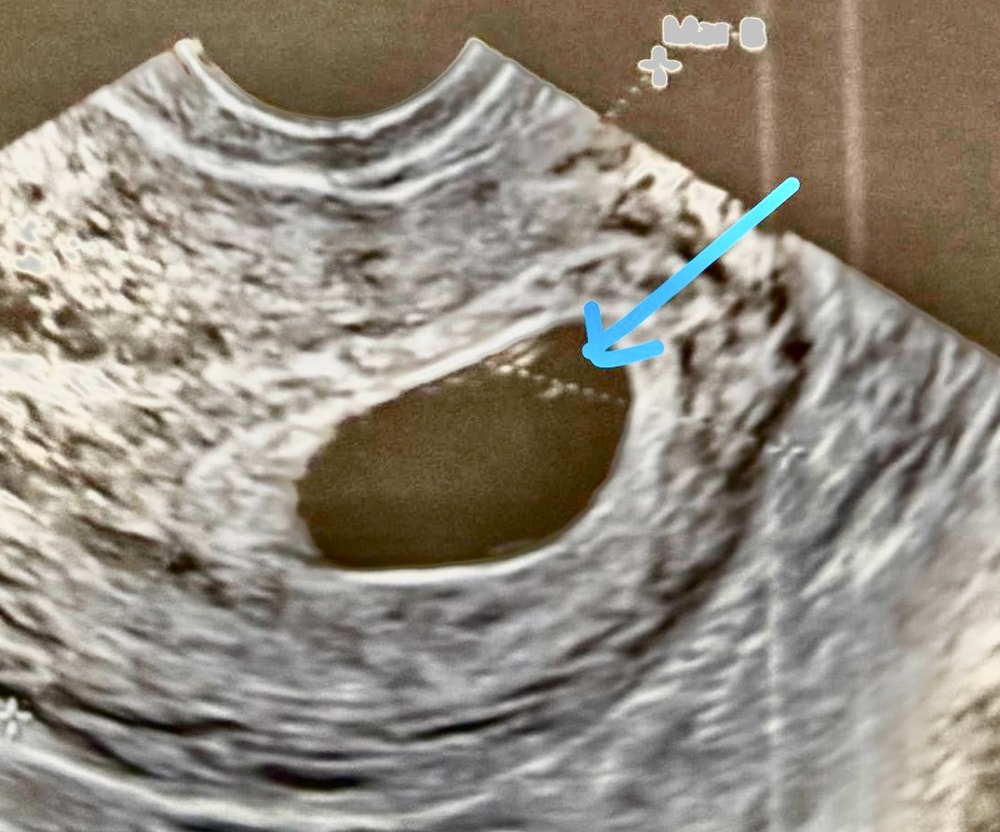

Это же желточный мешок да??

28.06 была на узи, поставили заключение замершая беременность в сроке 6-7 недель , анэмриония. Плодной яйцо 21,4 мм. Сказала идти на чистку.

Но после осмотра смотрю на фото узи и вижу такую картину. Как можно такое не увидеть?Я же не одна вижу? Как увидела это кружочек чуть успокоилась🥹 и начала писать другим врачам. Все написали что «надо на повторное узи, а на чистку не ходите ни в коем случай. Ещё рано так твердить и тем более отправлять на чистку»

У меня тоже анэмбриония была с желточным мешочком.